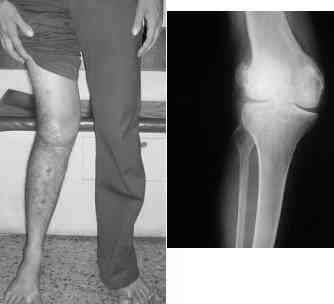

This 20 year old patient sustained a fracture in the lower end of the femur, one and a half years ago, with a compound wound over the fracture area.

Notes at that time mention a compound fracture dislocation, with a loss of part of the lateral condyle. This was treated by debridement, and external fixation. After two weeks, the lateral condyle (coronal fracture) was fixed by a screw and k wire in an AP direction.

At present, he has a valgus deformity of the knee, with 0-45 degrees of movt. The knee is stable to examination, could not be corrected to neutral from the existing valgus, and despite the deformity he is walking on it, albeit with pain and some difficulty.